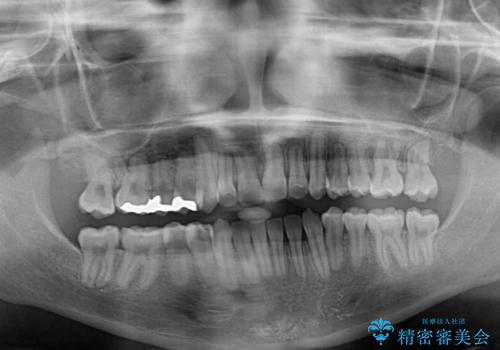

急速拡大装置により骨格はある程度改善されましたが、奥歯の咬み合わせ改善に非常に時間がかかってしまいました。

デコボコを改善させるだけでなく、しっかりとした咬合状態を獲得することができ、患者様には大変満足していただけました。